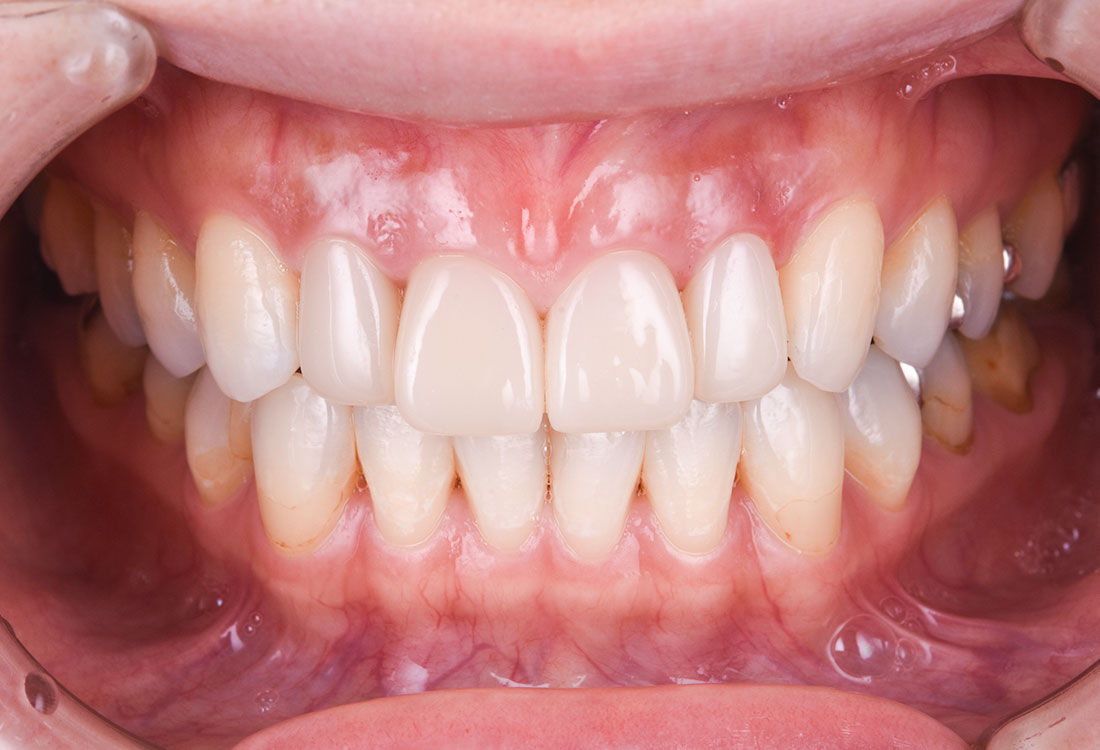

治療後

白く明るい口元になりました。